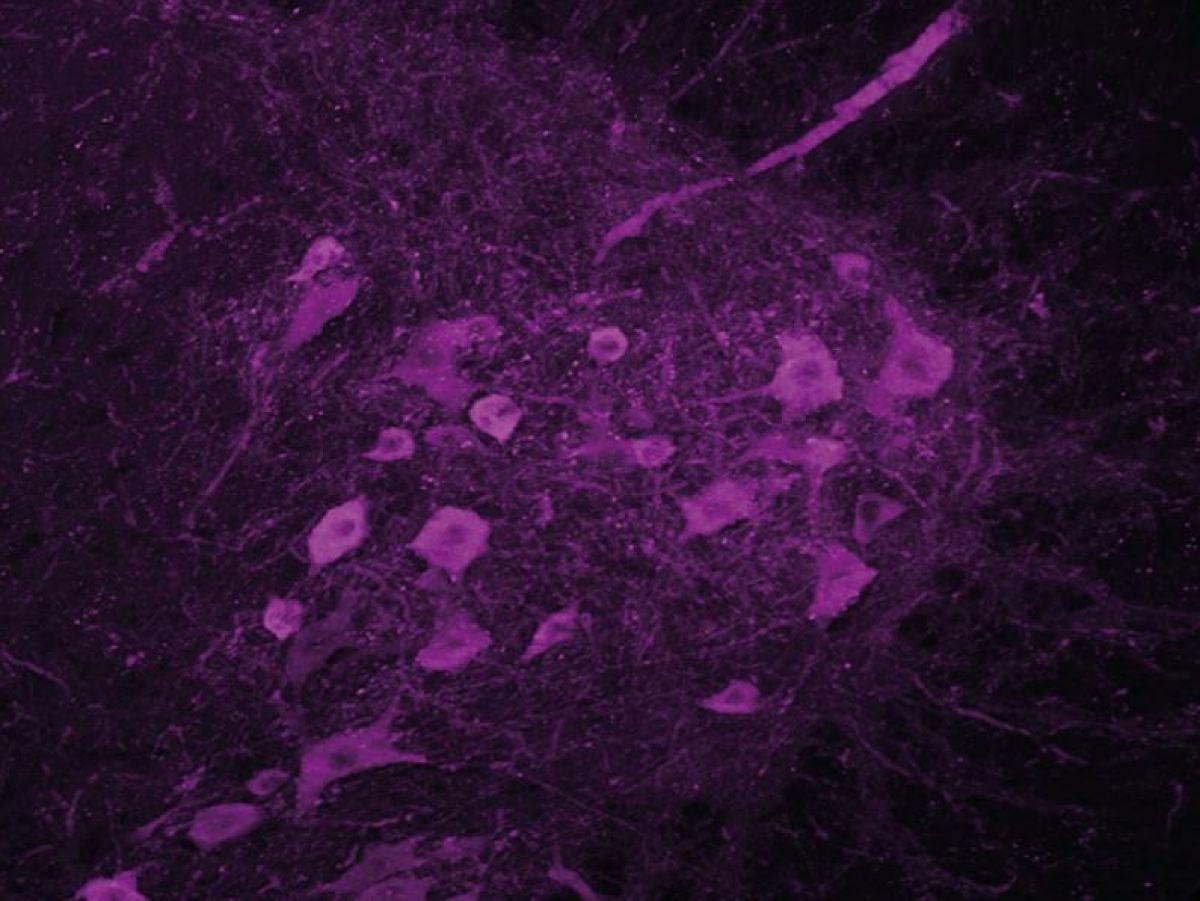

Il existe deux types de neurones moteurs (ou motoneurones): les neurones moteurs centraux, situés dans le cortex moteur, qui envoient les ordres de contraction à la moelle épinière, et les neurones moteurs périphériques, qui transmettent ces commandes aux muscles. Chez un patient atteint de la SLA, les deux dégénèrent, ce qui coupe la communication entre le cerveau et les muscles. Non sollicités, ces derniers ne se contractent plus et finissent par s’atrophier.

Pour leur étude, Matei Bolborea et son équipe ne se sont pas concentrés spécifiquement sur les neurones moteurs, mais des neurones de l’hypothalamus. Il y a quelques années, cette même équipe avait mis en évidence une perte de poids très précoce chez les patients, indépendamment de toute atteinte motrice.

« C’est pour cela que nous nous sommes intéressés à l’hypothalamus, qui est la structure du cerveau en charge de la régulation de notre poids. Nous avons observé que les neurones exprimant l’orexine et la melanin-concentrating hormone (MCH), molécules qui régulent la prise alimentaire mais aussi l’activité et le sommeil, étaient altérés chez les personnes atteintes de SLA, raconte le chercheur. Naturellement, s’il y a des troubles de l’expression de ces neurotransmetteurs dans le cerveau, il y a sûrement aussi des problèmes de sommeil. »

Les souris traitées récupèrent un meilleur sommeil, et leur motoneurone est préservé. »Les motoneurones lombaires semblent ne plus mourir. Ils sont bien là, mais on ne sait pas s’ils sont encore fonctionnels. »